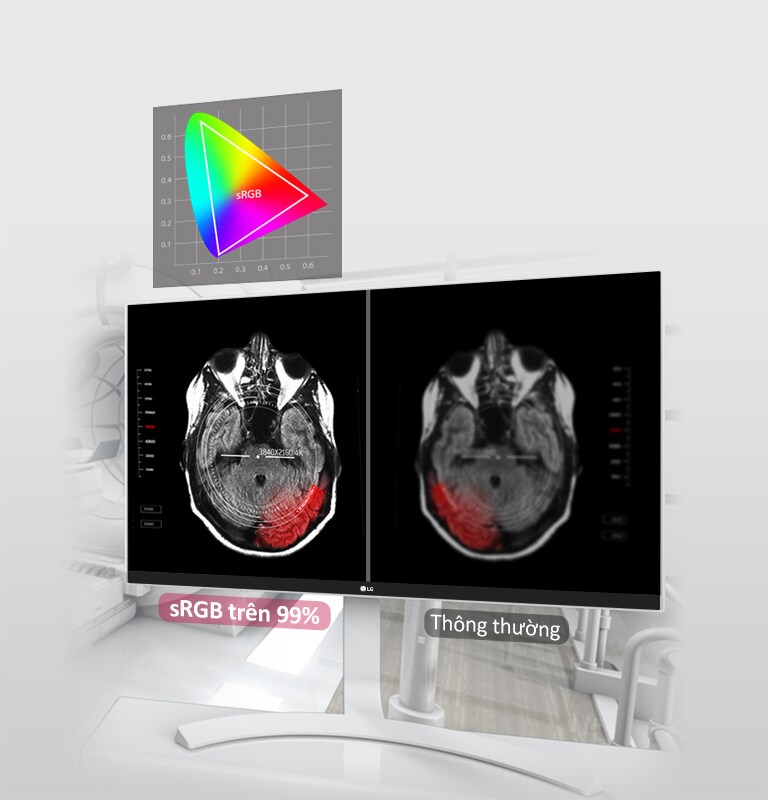

Gam màu (Điển hình)

sRGB 99% (CIE1931)